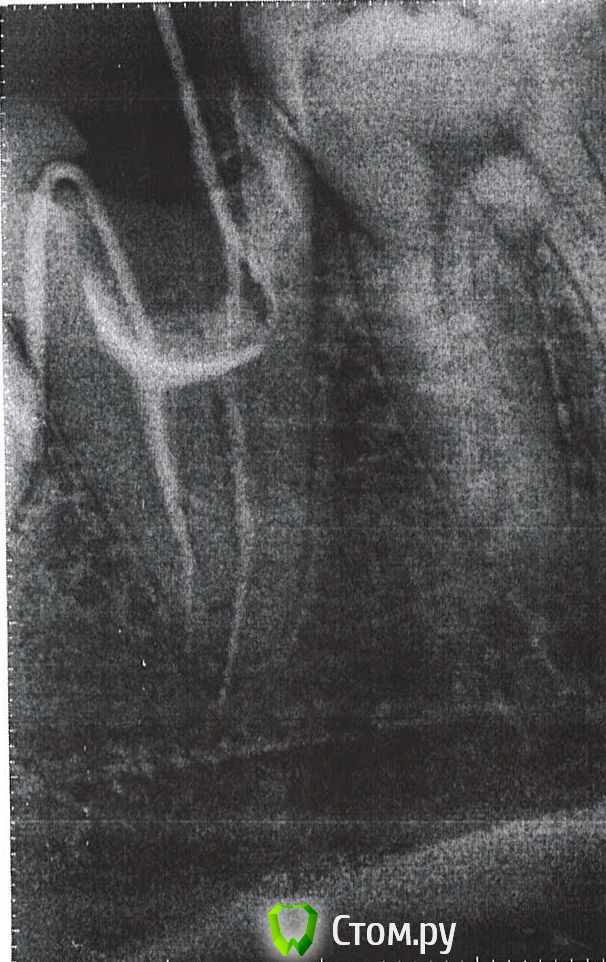

FJoe Опубликовано 21 августа, 2014 Автор Поделиться Опубликовано 21 августа, 2014 Прилагаю снимок.Тут уже с гуттаперчей. Ссылка на комментарий

Гарриевич Опубликовано 21 августа, 2014 Поделиться Опубликовано 21 августа, 2014 по вопросам:1- что то пошло не совсем так2-выход инструмента это не хорошо3- является4- на изоляцию коффердамомпо снимку:нет изоляции зуба - это минусгуттаперча на припасовке вышла за пределы корня - это минусскорее всего боли связаны с тем что инструментами повредили периодонт - это не смертельно 2 Ссылка на комментарий

FJoe Опубликовано 21 августа, 2014 Автор Поделиться Опубликовано 21 августа, 2014 Коффердам в данной клинике, видимо, не используется. В следующий раз иду уже пломбироваться.Что делать, если на итоговом снимке гуттаперча там и останется? Чем это чревато? И еще: мне кажется или каналы на снимке как бы соединены? (тёмная поперечная полоса) Ссылка на комментарий

Гарриевич Опубликовано 21 августа, 2014 Поделиться Опубликовано 21 августа, 2014 чревато осложнениями и очень неблагоприятным прогнозом Ссылка на комментарий

Scrabble Опубликовано 21 августа, 2014 Поделиться Опубликовано 21 августа, 2014 Тёмная полоса может быть просто тёмной полосой-это не суть. Главное, чтобы каналы были отлично вымыты, что без коффердама сложно осуществить. Ссылка на комментарий